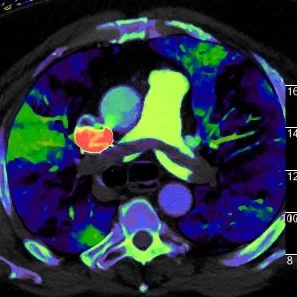

Spectral image with perfusion overlay shows with extensive perfusion defects (normal perfusion is green).